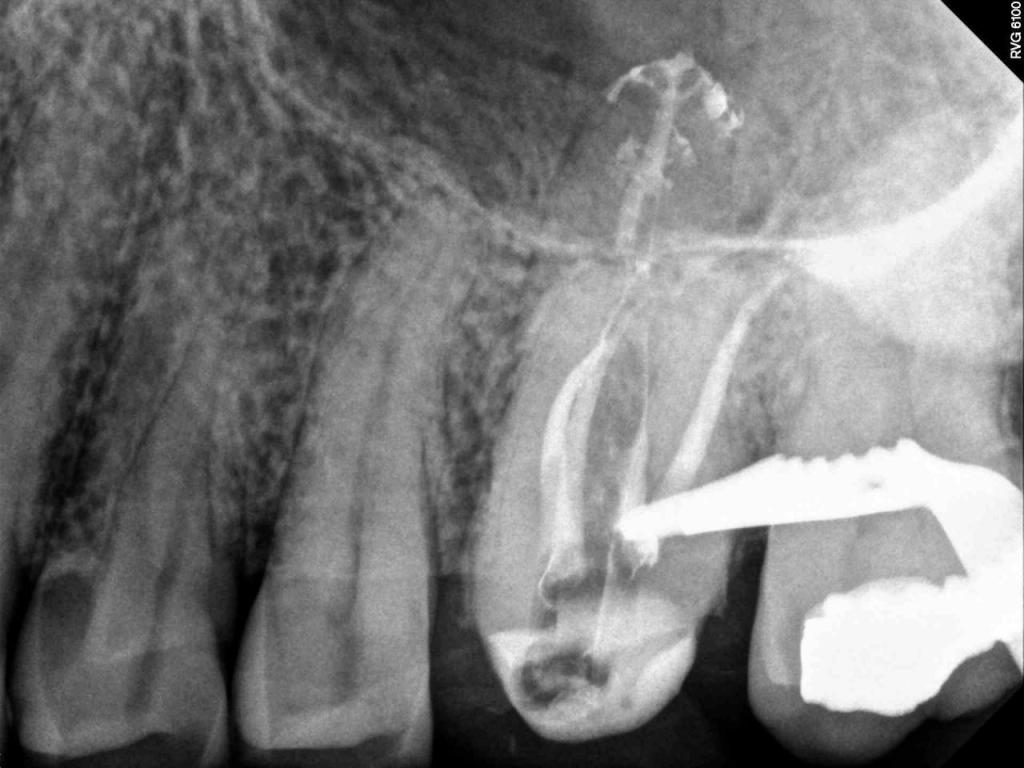

Although the primary use of visual documentation is for patient charts, dental images provide a meaningful way to communicate with patients about their care needs. Digital imagery is a vital tool for educating patients and an essential way to share information with office staff, colleagues and referring doctors. Digital technology has allowed Southcenter Endodontics to enhance our practice and improve the delivery of care to our patients. Below you will see images of “Before” and “After” scenarios. By clicking on a thumbnail image below, you will be able to see and a larger view of the x-ray taken at Southcenter Endodontics and notations made regarding each film.